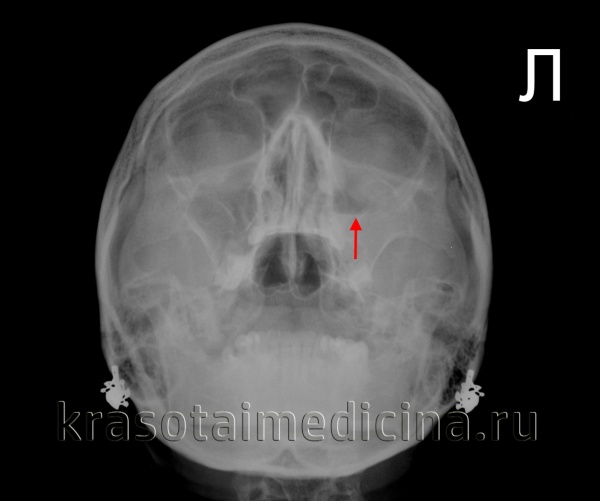

Диагностические методы выявления острого гайморита согласно МКБ-10

Диагноз «острый гайморит» ставится на основании осмотра, риноскопии и жалоб пациента. Опытный доктор сразу скажет, что вы «владелец» гайморита. Для подтверждения диагноза могут быть назначены дополнительные методы диагностики:

- рентгенография верхнечелюстного синуса;

- обзорная рентгенография околоносовых пазух;